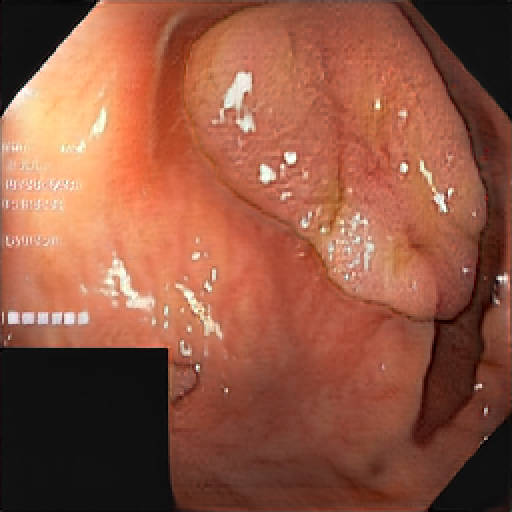

We have used a polyp dataset published with HyperKvasir dataset [51], which consists of polyp findings extracted from endoscopy examinations. HyperKvasir contains polyp images with corresponding segmentation masks annotated by medical experts. We use only this polyp dataset as a case study because of the time and resource-consuming training process of the SinGAN-Seg pipeline. However, the SinGAN-Seg model and pipeline can be used for any segmentation dataset.

A few sample images and the corresponding masks of the polyp dataset in HyperKvasir are shown in Fig 2. The polyp images are RGB images. The masks of the polyp images are single-channel images with white () for true pixels, which represent polyp regions, and black () for false pixels, which represent clean colon or background regions. In this dataset, there are different sizes of polyps. The distribution of polyp sizes as a percentage of the full image size is presented in the histogram plot in Fig 3, and we can observe that there are more relatively small polyps compared to larger polyps. Additionally, a subset of this dataset was used to prove that the performance of segmentation models trained with small datasets can be improved using our SinGAN-Seg pipeline, and the whole dataset was used to show the effect of using SinGAN-Seg generated synthetic images instead of a large dataset which has enough data to train segmentation models. In this regard, this dataset was used for two purposes: